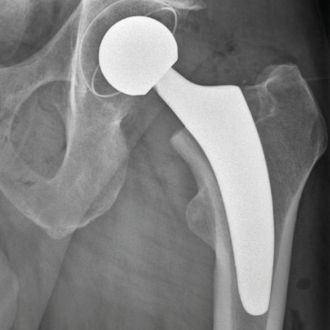

Hüftendoprothetik

Minimalinvasive Operationstechniken ermöglichen einen schonenden Hüftgelenkersatz – für eine schnellere Genesung und mehr Mobilität im Alltag.